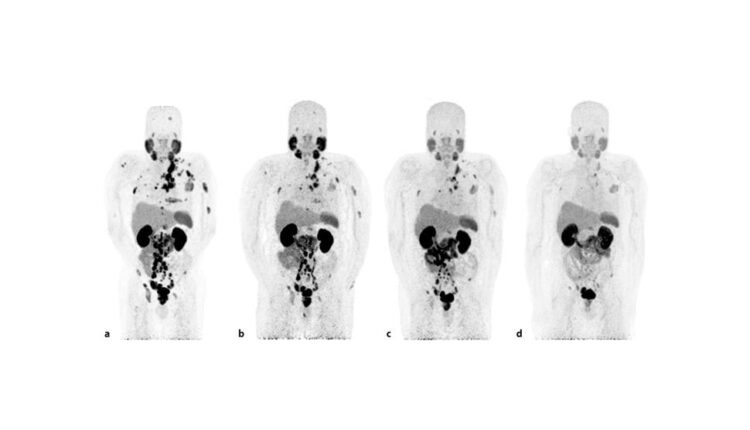

PSMA PET-CT